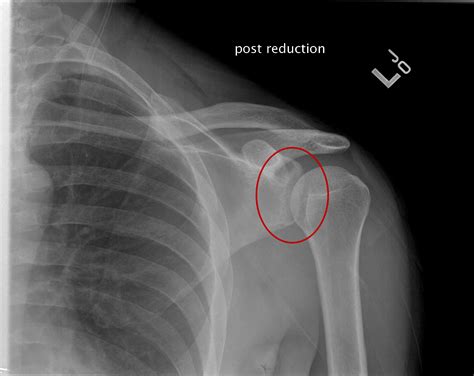

When a shoulder X-ray normal result is reported, it means that the X-ray images do not show any visible abnormalities in the bones or joints. This can be reassuring for patients experiencing shoulder pain, as it indicates that there are no obvious fractures or dislocations. However, it is important to note that a normal X-ray does not rule out all possible causes of shoulder pain.

• No Dislocations: The bones are properly aligned, indicating that there is no dislocation of the shoulder joint.

• Computed Tomography (CT) Scan: A CT scan uses X-rays to produce detailed images of the bones and joints. This test can help identify fractures, dislocations, and other bone abnormalities that may not be visible on a standard X-ray.